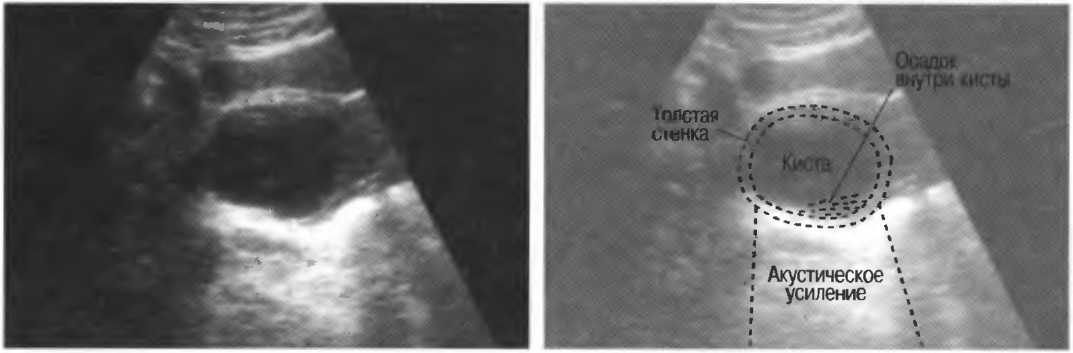

Кисты

Киста, как правило, визуализируется в виде анэхогенной зоны, при этом структуры, расположенные за кистой, обычно усилены: полость кисты анэхогенна, поскольку в ней нет структур с различным акустическим сопротивлением. В результате того что жидкость не поглощает ультразвук в такой же степени, что и ткань, эхо-сигналы от расположенных позади кисты структур гиперкомпенсированы сканером и выглядят усиленными — появляется эффект усиления задней стенки (рис. 14а,б).

Киста определяется в виде анэхогенной зоны с усилением по задней стенке. Если в кисте есть внутренние зхоструктуры, то они могут быть реальными или являться артефактами.

Рис. 14а. Заполненная жидкостью киста: полость кисты анзхогенна, имеется усиление задней стенки.

Рис.14б. Данная киста яичника имеет толстые стенки и внутренний осадок, создающий внутреннюю эхоструктуру, перемещающуюся при перемене положения тела пациента.

Структура, наподобие содержащей чистую жидкость кисты, визуализируется как анэхогенная зона. Стенки кисты отражают ультразвуковые сигналы под углом, и информация не поступает назад в трансдьюсер. В результате этого появляются боковые тени, но сзади кисты имеется усиление эхосигналов (усиление задней стенки) (рис. 15).

Рис. 15а. Киста печени: жидкость внутри чистая, анэхогенная. Стенки кисты отражают ультразвук под углом от датчика, вызывая появление боковых теней.

Рис. 15б. Плодные яйца при анэмбрионии: две жидкостьсодержащие структуры с задним усилением и латеральными тенями.

Артефакты могут определяться в любой кистозной структуре (такой, например, как мочевой пузырь или желчный пузырь) и чаще определяются ближе кпереди, становясь менее выраженными на глубине. Они исчезают или меняют свой характер при изменении положения датчика. Но истинные структуры в кисте, такие как перегородки, сохраняют свое местоположение независимо от положения датчика. Истинные отражения имеют место при наличии сгустка крови, гноя, некротической взвеси, и все это чаще визуализируется по задней стенке: если эти структуры не фиксированы к стенке, они изменяют свое положение при перемене положения тела пациента (рис. 16).

Осадок в кисте может флотировать, формируя уровень, изменяющий свое положение при перемещении пациента (рис. 16б,в).

Рис. 16б. Киста с усилением по задней стенке, латеральными тенями и осадком в полости.

Рис. 16в. Этот же пациент, что и на рис. 16б. Сканирование осуществляется в разных положениях больного. Уровень, создаваемый осадком, смещается.